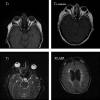

El contraste aumenta la sensibilidad y especificidad de la TC, y debe ser solicitado en muchas de las ocasiones. La alta densidad radiológica del hueso y la sangre hacen que la visualización de la hemorragia durante la fase aguda, la neuropatía óptica traumática o la fractura orbitaria sean algunas de las situaciones en las que no se precisa el uso de contraste (fig. 1).

Fig. 1: La presencia de cuerpo extraño intraocular (1), las drusas papilares

(2), la oftalmopatía distiroidea (3), el traumatismo orbitario con sospecha de

fractura orbitaria (4), y el sangrado reciente (5) son algunas de las escasas

situaciones en las que la TC puedc ser superior a la RM. En ninguna de estas

situaciones se precisa el uso de contraste.